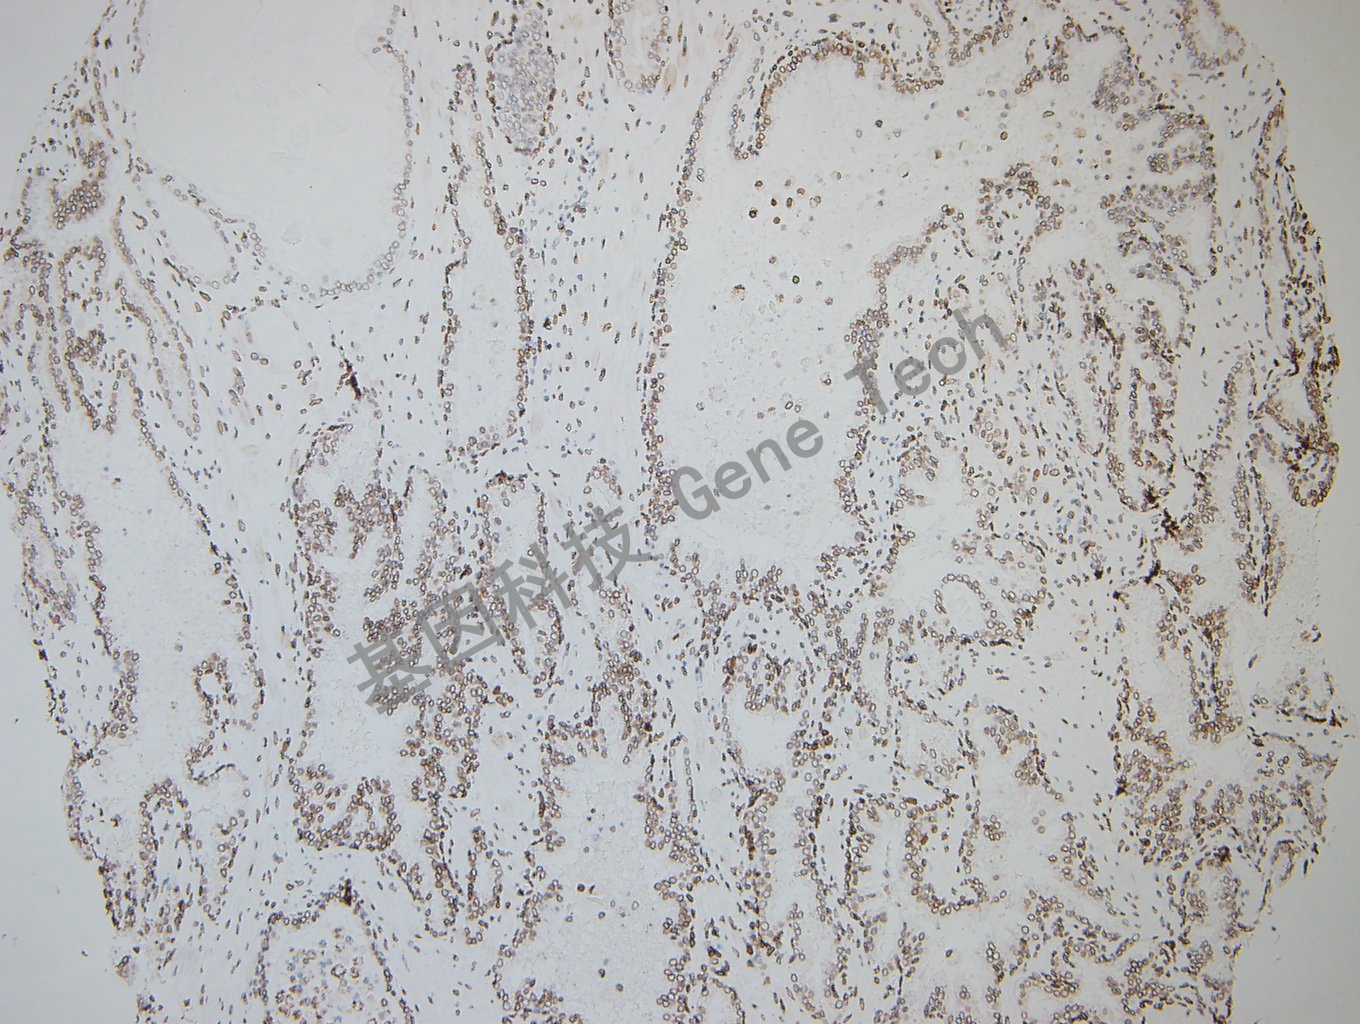

结直肠癌石蜡切片,用 GATA2(GT2320)染色,细胞核阳性,DAB 显色。